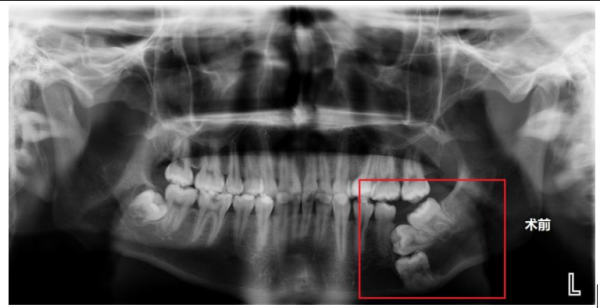

术前X片显示,右下颌骨内没长出来的三颗磨牙呈“叠罗汉”状埋伏

据了解,家住益阳市的王其(化名)自6岁起左下磨牙一直未萌出,家长起初以为仅是发育较晚,未予重视。直至14岁时,王其的磨牙仍未见生长,父母这才带着他去当地医院检查,完善了口腔X片后才发现,王其多年无牙的罪魁祸首竟是其右下颌骨内没长出来的三颗磨牙呈“叠罗汉”状埋伏,由于埋伏牙位置较深,当地医院建议在面部下方皮肤行切口拔除埋伏牙,或者继续观察,等待恒牙自行萌出。因考虑传统手术可能遗留面部瘢痕,王其及家人选择保守观察。